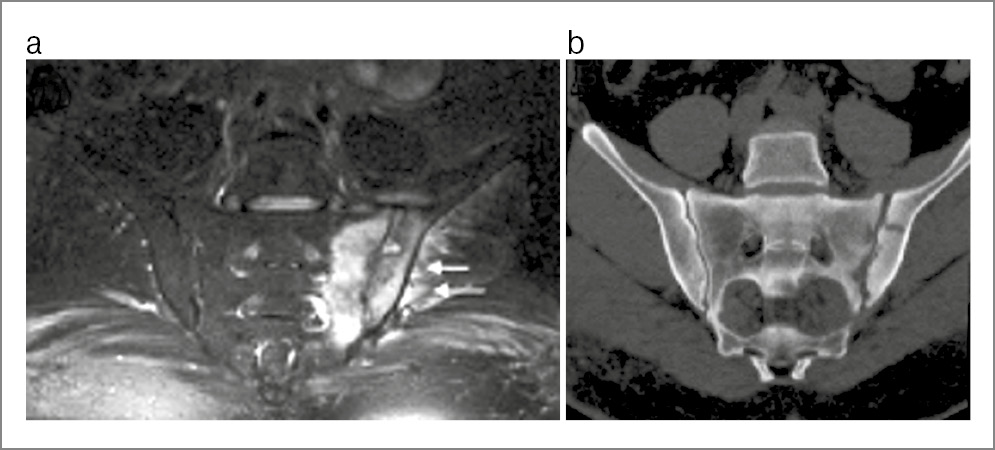

Рис. 14. Пациент А. 20 лет, длительность болей в нижней части спины 5 лет. МРТ КПС в коронарной проекции: a – в режиме Т2 FatSat в левой боковой массе крестца на уровне верхних отделов сустава отмечается зона отека костного мозга, также создается впечатление об усилении сигнала от прилежащих мягких тканей (указано стрелками); b – в режиме Т1 отчетливо визуализируется неоартроз между левым поперечным отростком позвонка LV и левой боковой массой крестца (стрелка) – левосторонняя сакрализация LV с признаками отека.

Люмбосакральный переходный позвонок. Пояснично-крестцовый переходный позвонок (вариант развития) наблюдается в общей популяции примерно у 25% пациентов. Возможна либо сакрализация тела пятого поясничного позвонка, либо люмбализация позвонка SI. Анатомические варианты разнообразны: от расширенных поперечных отростков до полного слияния их с крестцом с двух сторон или с одной стороны (рис. 14). Переходные позвонки могут сопровождаться болями в пояснице, особенно если имеется неполное сращение (псевдоартроз) между увеличенными поперечными отростками и верхней частью крестца.